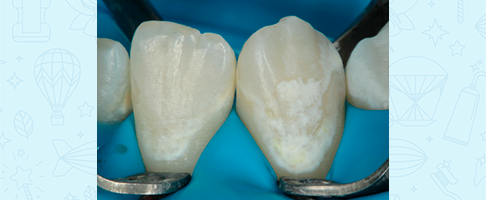

Профессиональная гигиена сменного прикуса

Профессиональная гигиена сменного прикуса

Профессиональная гигиена сменного прикуса